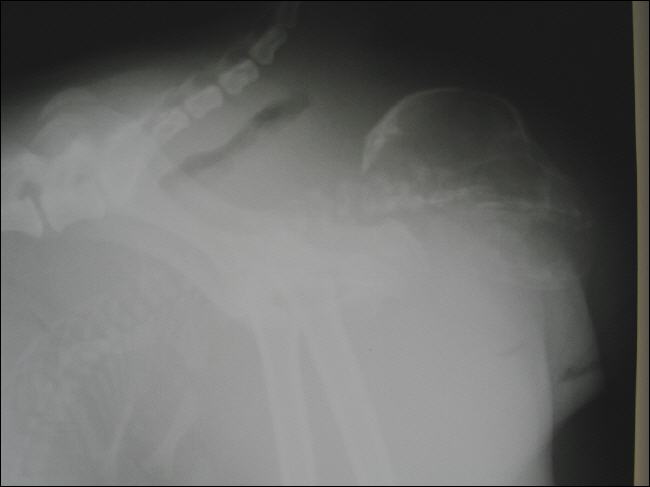

Welpe im Geburtskanal

Röntgenbild eines Hundewelpen während der Geburt